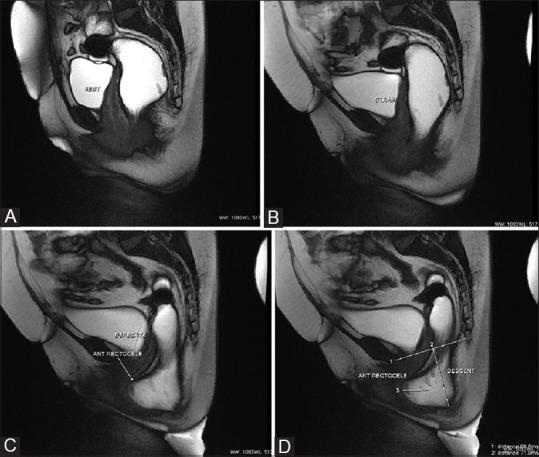

用于排便障碍综合征的磁共振排粪造影

MR defecography for obstructed defecation syndrome.

Patients with obstructed defecation syndrome (ODS) form an important subset of patients with chronic constipation. Evaluation and treatment of these patients has traditionally been difficult. Magnetic resonance defecography (MRD) is a very useful tool for the evaluation of these patients. We evaluated the scans and records of 192 consecutive patients who underwent MRD at our center between January 2011 and January 2012. Abnormal descent, rectoceles, rectorectal intussusceptions, enteroceles, and spastic perineum were observed in a large number of these patients, usually in various combinations. We discuss the technique, its advantages and limitations, and the normal findings and various pathologies.

摘要

排便梗阻综合征(ODS)患者是慢性便秘患者中的一个重要亚组。传统上,对这些患者的评估和治疗一直很困难。磁共振排粪造影(MRD)是评估这些患者的非常有用的工具。我们评估了2011年1月至2012年1月期间在我们中心接受MRD检查的192例连续患者的扫描结果和记录。在这些患者中,大量观察到异常下降、直肠膨出、直肠直肠套叠、肠膨出和会阴痉挛,通常是多种情况并存。我们讨论了该技术、其优点和局限性,以及正常表现和各种病变。